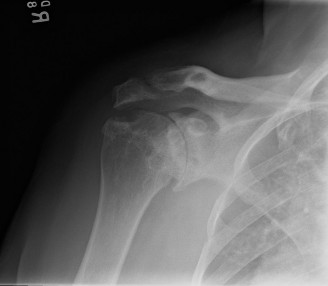

A 33-year-old male presents to the ED after a fall during a soccer game. He reports significant right shoulde…